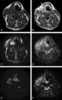

Hypopharyngeal tumor

Hypopharyngeal cancer is a disease in which malignant cells grow in the hypopharynx (also known as the laryngopharynx) the area where the larynx and esophagus meet.It first forms in the outer layer (epithelium) of the hypopharynx (last part of the pharynx), which is split into three areas. Progression of the disease is defined by the spread of cancer into one or more areas and into deeper tissues.This type of cancer is rare. [Source: Wikipedia ]